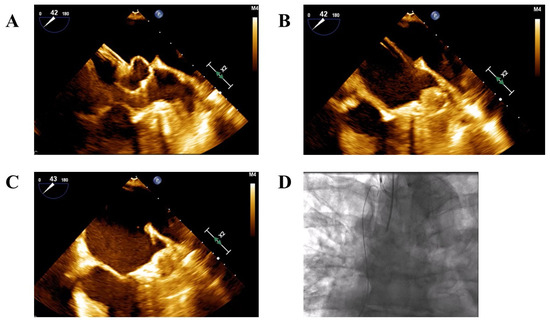

Long-Term Clinical Outcomes of Left Atrial Appendage Closure in Patients with Left Atrial Appendage Thrombus

Background: Patients with atrial fibrillation (AF) who have a high bleeding risk or contraindications to anticoagulation may be candidates for left atrial appendage closure (LAAC). However, the presence of a thrombus in the left atrial appendage (LAA) is generally considered a contraindication [...] Read more.

Background: Patients with atrial fibrillation (AF) who have a high bleeding risk or contraindications to anticoagulation may be candidates for left atrial appendage closure (LAAC). However, the presence of a thrombus in the left atrial appendage (LAA) is generally considered a contraindication to the procedure. While the feasibility and short-term safety of LAAC in patients with pre-existing LAA thrombus has been reported, data on long-term outcomes remain limited. Objective: To assess the long-term clinical outcomes of AF patients undergoing LAAC in the presence of an LAA thrombus. Methods: This retrospective, single-center registry included all AF patients who underwent LAAC between June 2010 and April 2024. Patients were stratified based on the presence or absence of LAA thrombus at the time of the procedure. The primary endpoint was a 5-year composite of stroke, systemic embolism, or all-cause mortality. Results: A total of 403 patients underwent LAAC, of whom 24 (6%) had an LAA thrombus at the time of the procedure. During a median follow-up of 3.9 years, the primary endpoint occurred in 116 patients: 110 events (41%) in the no-thrombus group and 6 events (38%) in the thrombus group. There was no statistically significant difference in major adverse cardiovascular events (MACE) between groups (log-rank p = 0.862). Conclusions: LAAC may be performed safely in selected patients with distal LAA thrombus, with long-term outcomes comparable to those without thrombus. Full article